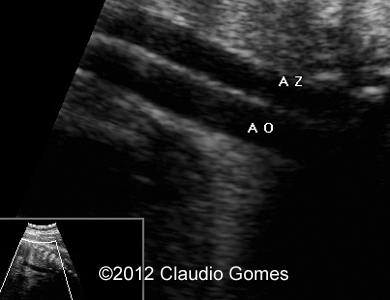

Image 2: Routine transverse view of the abdomen and thorax showing a vessel posterior and to the right of the aorta (Azygos vein).

Fig3

Images 4, 5: 26 weeks-Persistent right umbilical vein and again a vessel posterior and to the right of the aorta (Azygos vein).